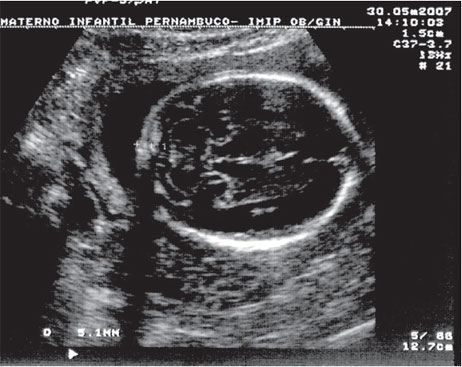

Figura 15.2: Avaliação do cerebelo, cisterna magna e prega nucal.